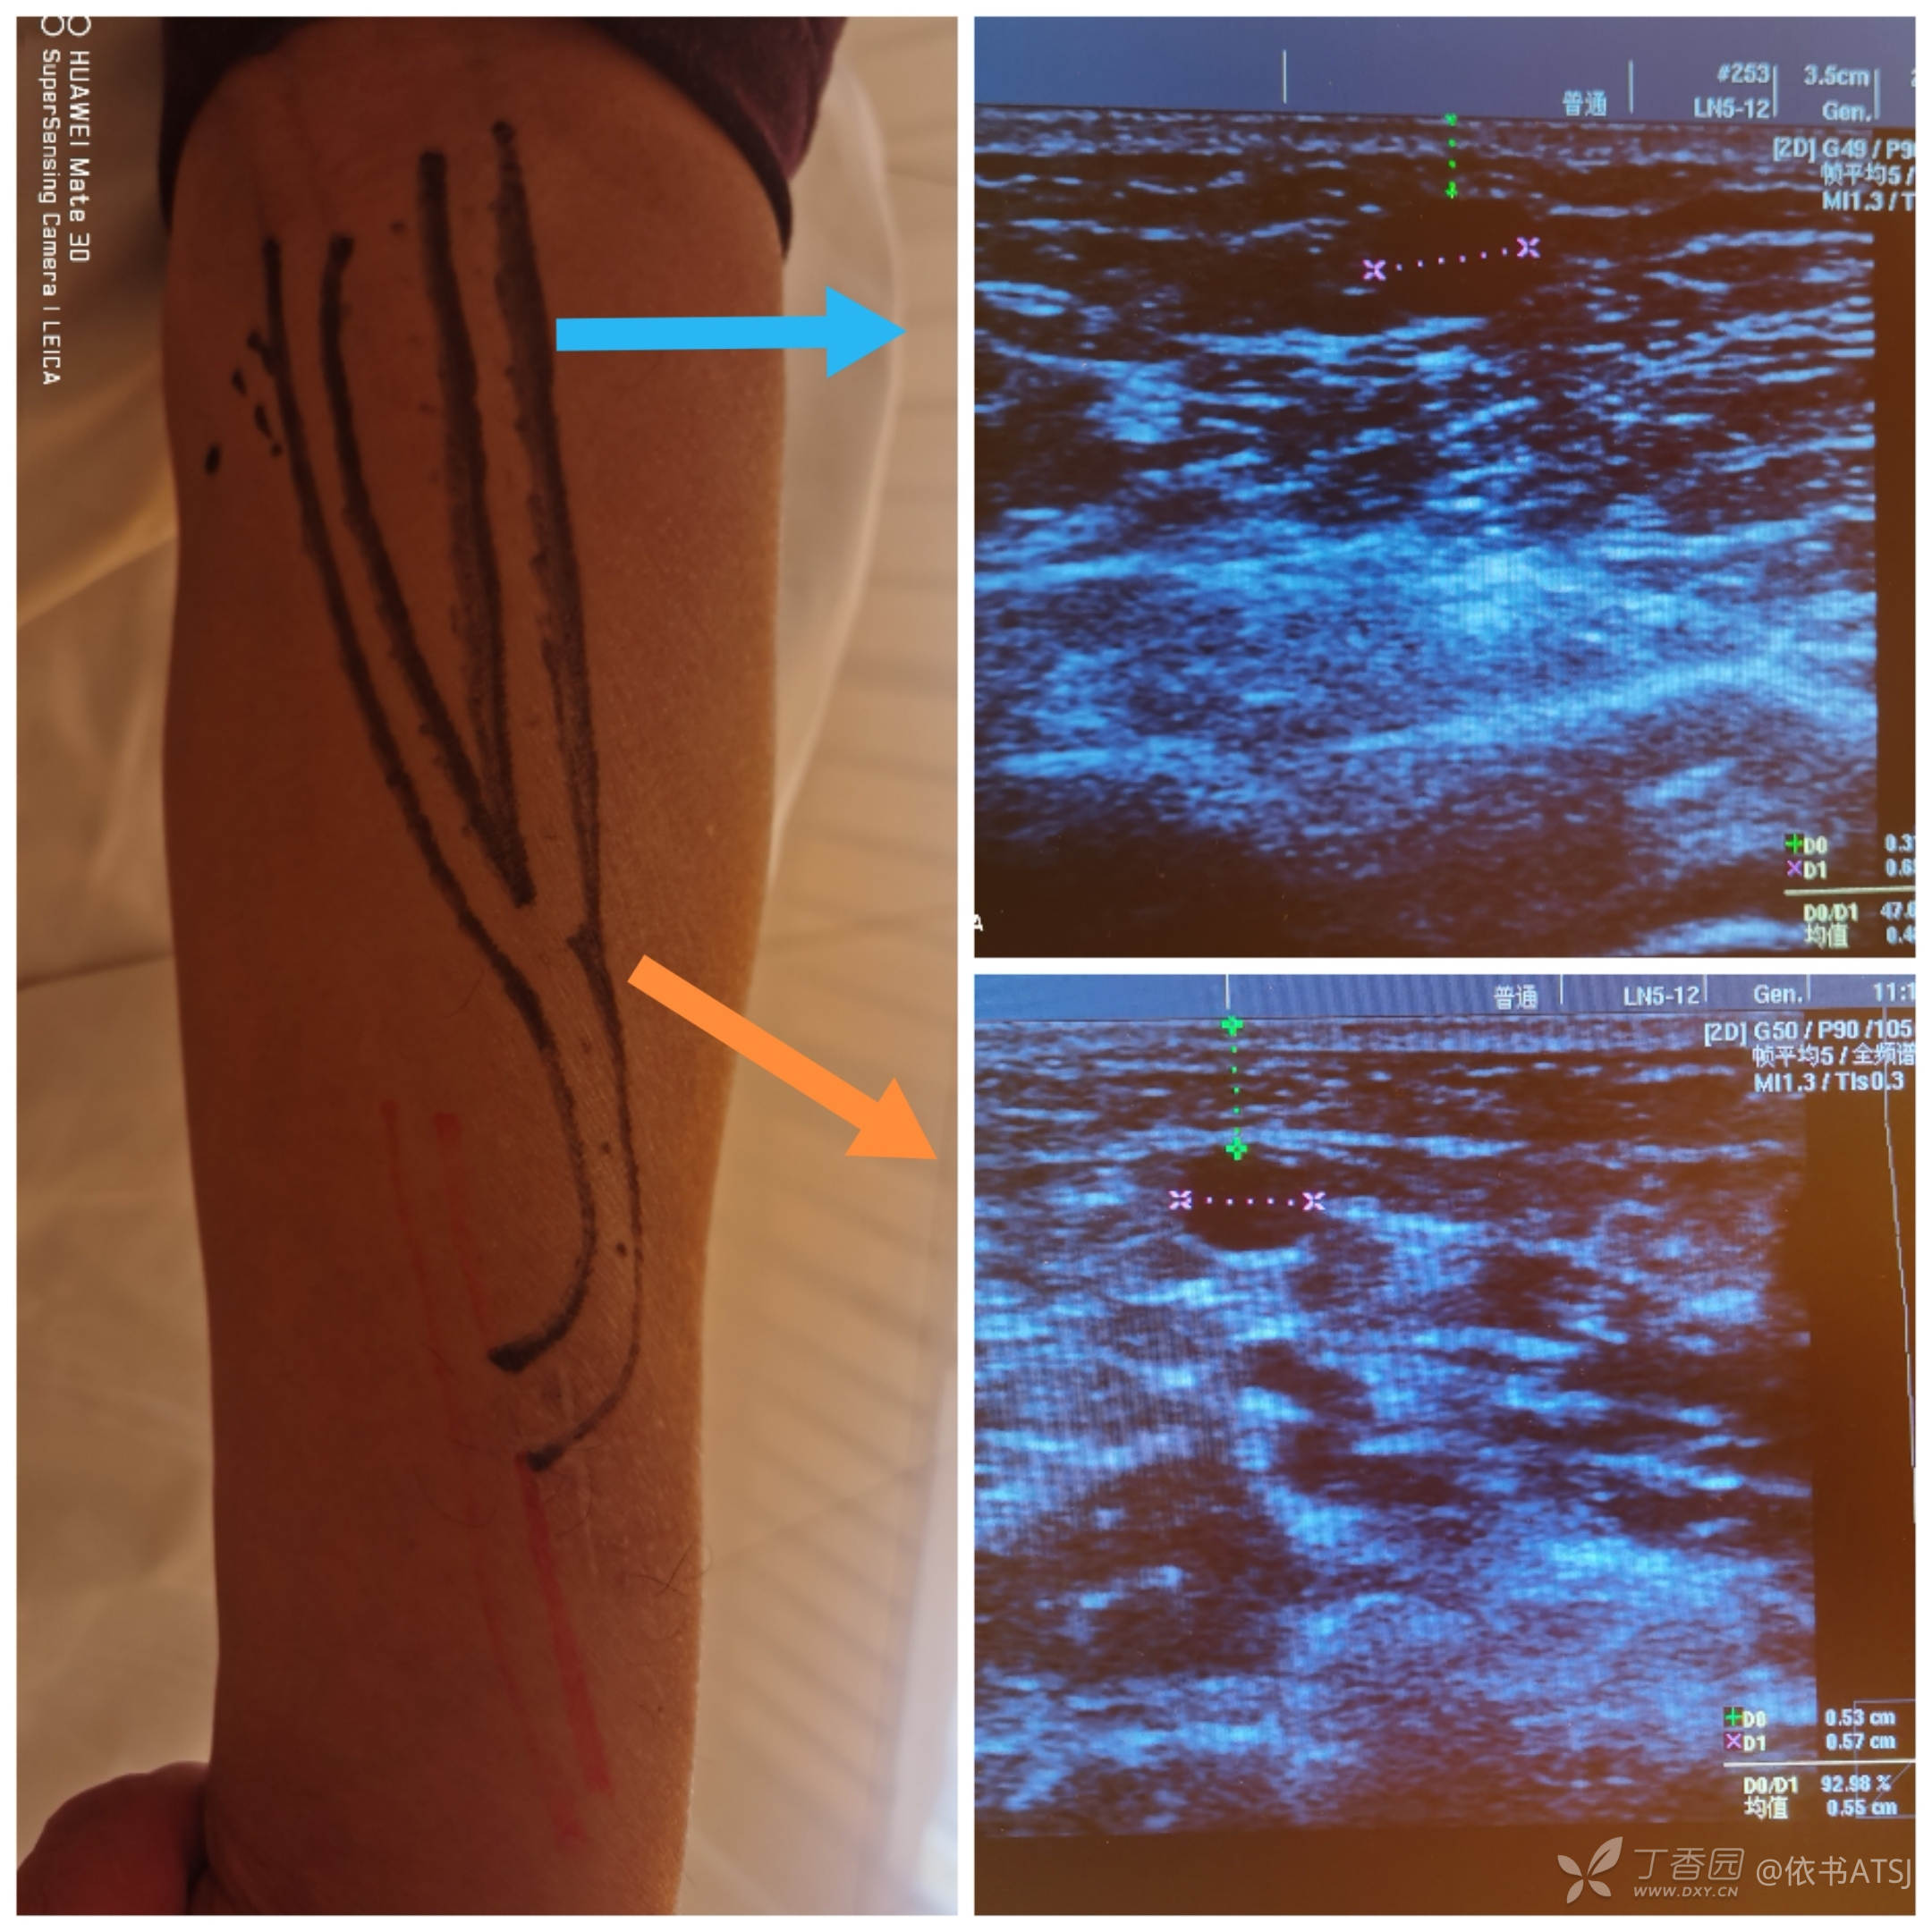

左前臂AVF,体型肥胖,水肿严重,血管打了彩超,给穿刺护士引路,安全第一。